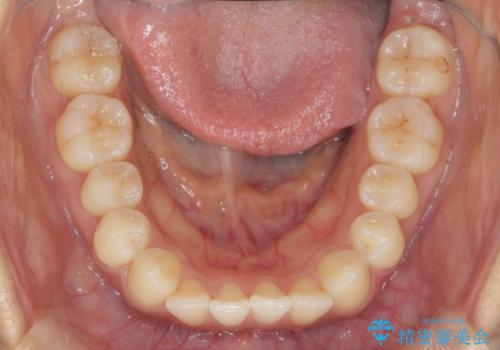

- 前歯のガタつき、上下たがい違いになっている歯並び(クロスバイト)の改善を求めて来院されました。

インビザラインによる矯正治療を行いますが、クロスバイトの改善をワイヤー部分矯正で事前に行うことにより治療期間の短縮する治療計画を立案します。

上下すれ違った噛み合わせはマウスピースでは改善に時間がかかり、またねじれが残ってしまうことも多々見られます。

マウスピース矯正を行う前に、これらの症状の改善の得意なワイヤー部分矯正を行うことで治療期間を短縮し、確実にすれ違いを改善することができます。